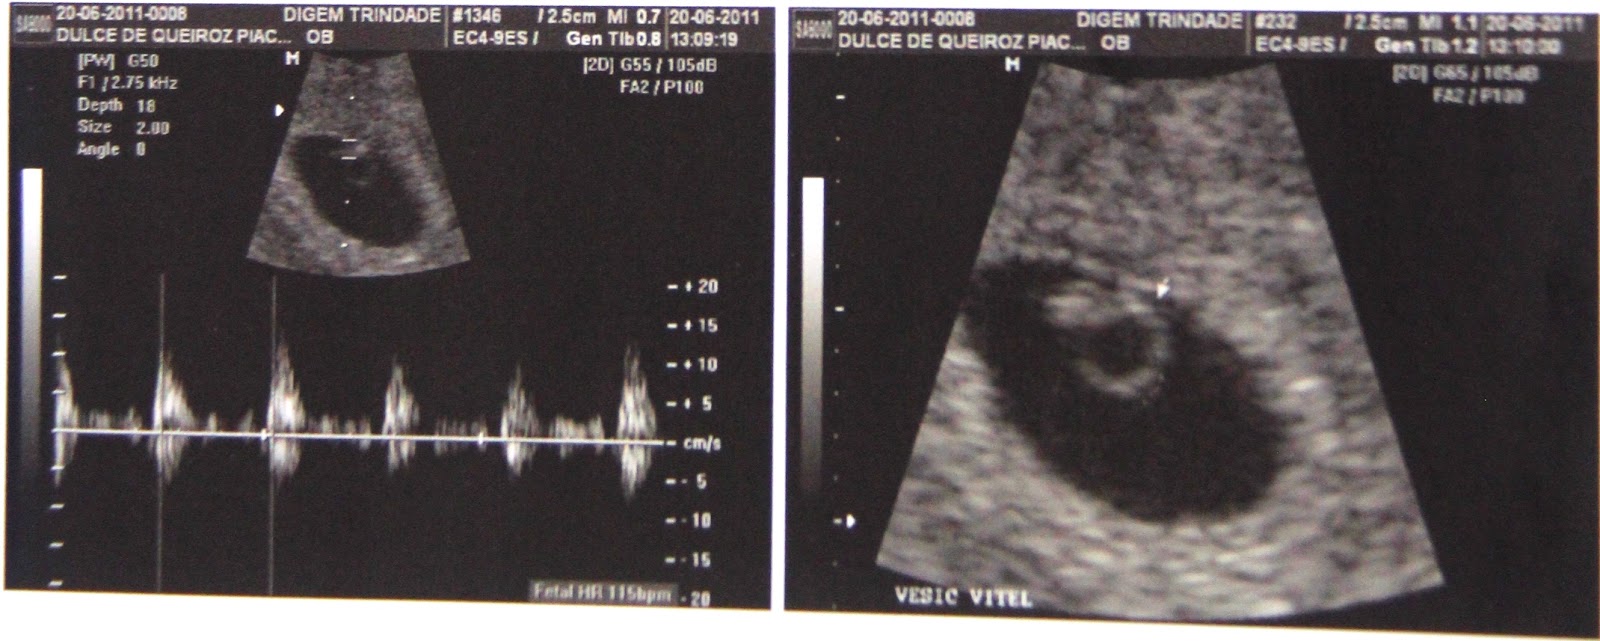

Vídeo de ultrassom mostra bebê de 11 semanas pulando no ventre materno

Breve exibição de uma criança se mexendo na barriga de sua mãe fica viral na Internet. A imagem tirada de uma ultrassonografia ...